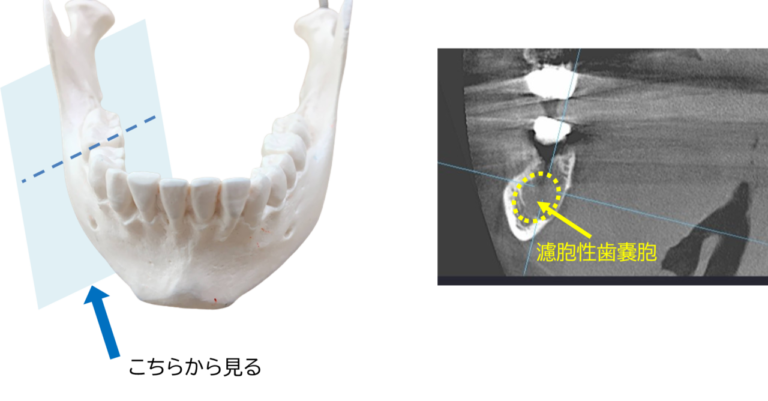

場合によっては、定期的な健康診断で医師が濾胞性嚢胞があることを知ることがあります。あなたが出産可能な年齢で、それ以外は健康で、何の症状も示さない場合、医師は嚢胞が自然に解決するまで放置する可能性があります。定期検査の際にそれが成長していないことを確認するために監視する場合があります。場合によっては、膣超音波検査やその他の検査も推奨される場合があります。

下腹部の痛みやその他の症状がある場合、医師は原因を診断するために内診を行うことがあります。症状や病歴に応じて、超音波検査、CT スキャン、MRI スキャン、その他の検査も推奨される場合があります。医師が正確な診断を下すことが重要です。破裂した嚢胞の症状は、多くの場合、虫垂炎や他のいくつかの病気の症状と似ています。